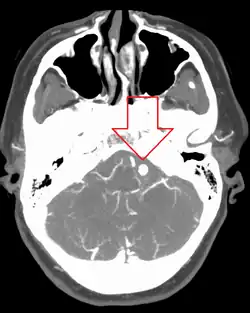

![]() | |

| Angiography of an aneurysm in a brain artery. The aneurysm is the large bulge in the center of the image. | |